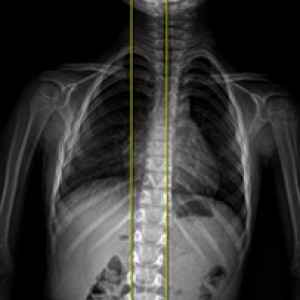

검사부터 다른 당당

“당당은 뼈만 보지 않습니다.”

근육과 근막의 정렬을 함께 진단하며, 풀 스파인 촬영을 통해 머리부터 모든 고관절, 발의 정렬까지 함께 파악하여 개개인에 맞는 전신 치료법을 설계합니다.

전신 엑스레이 검사

다리길이 엑스레이 검사

해당 사진은 수정없는 실제 치료사진입니다.

환자의 치료결과는 환자의 상태, 치료방법 등에 따라 차이가 발생할 수 있습니다.